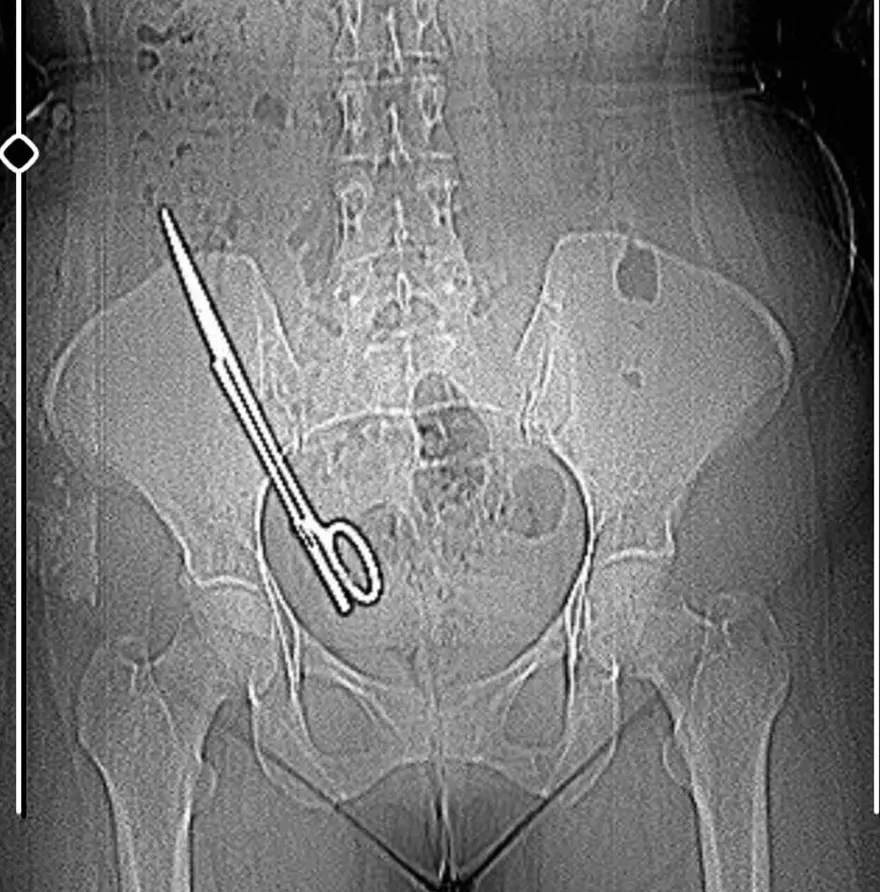

Kahramanmaraş’ta baş ağrısı şikayetiyle hastaneye giden Fatma Kala'nın (36) karnında 16 santimetre uzunluğunda ameliyat makası tespit edildi. 7 yıl önce geçirdiği kist ameliyatı sonrası karnında makas unutulduğu ortaya çıkan Kala, ameliyatı yapan doktor hakkında savcılığa suç duyurusunda bulunduğunu belirterek, “Hep haberlerde duyuyordum böyle olayları, ameliyatta sargı bezi, iğne aynı şeyin daha fazlası başıma geldi maalesef. Ben 7 yıl boyunca mucize eseri hayatta kalmışım” dedi.

İddiaya göre; Koray Ş., 7 yıl önceki ameliyattan dolayı bir komplikasyon oluştuğunu ve acilen ameliyat etmesi gerektiğini söyledi. Doktorun tavırlarından şüphelenen Fatma Kala, ameliyat olmayı reddedip KSÜ Sağlık Uygulama ve Araştırma Hastanesi'ne gitti. Burada yapılan tetkiklerde Kala’nın karnında 16 santimetre uzunluğunda makas olduğu tespit edildi.

Doktorumuz bizi hemen röntgene aldı. Röntgende bir yabancı cisim görmüş ama bize söylemedi, ‘Daha önceki ameliyatından dolayı bir komplikasyon oluşmuş. Seni ameliyat edip dedi o komplikasyonu ortadan kaldırmam gerekiyor’ dedi. Biz doktorun telaşlı tavrından şüphelendik. Eşimle birlikte tıp fakültesine gittik. Oradaki acil doktorlarına başımızdan geçen olayı anlattık. Onlar beni röntgene soktu. Oradan ilaçlı tomografiye girince daha önceki ameliyatımda bırakılan makas orada görüldü. Genel cerrahi bölümünde bu makas çıkarıldı'' diye konuştu.